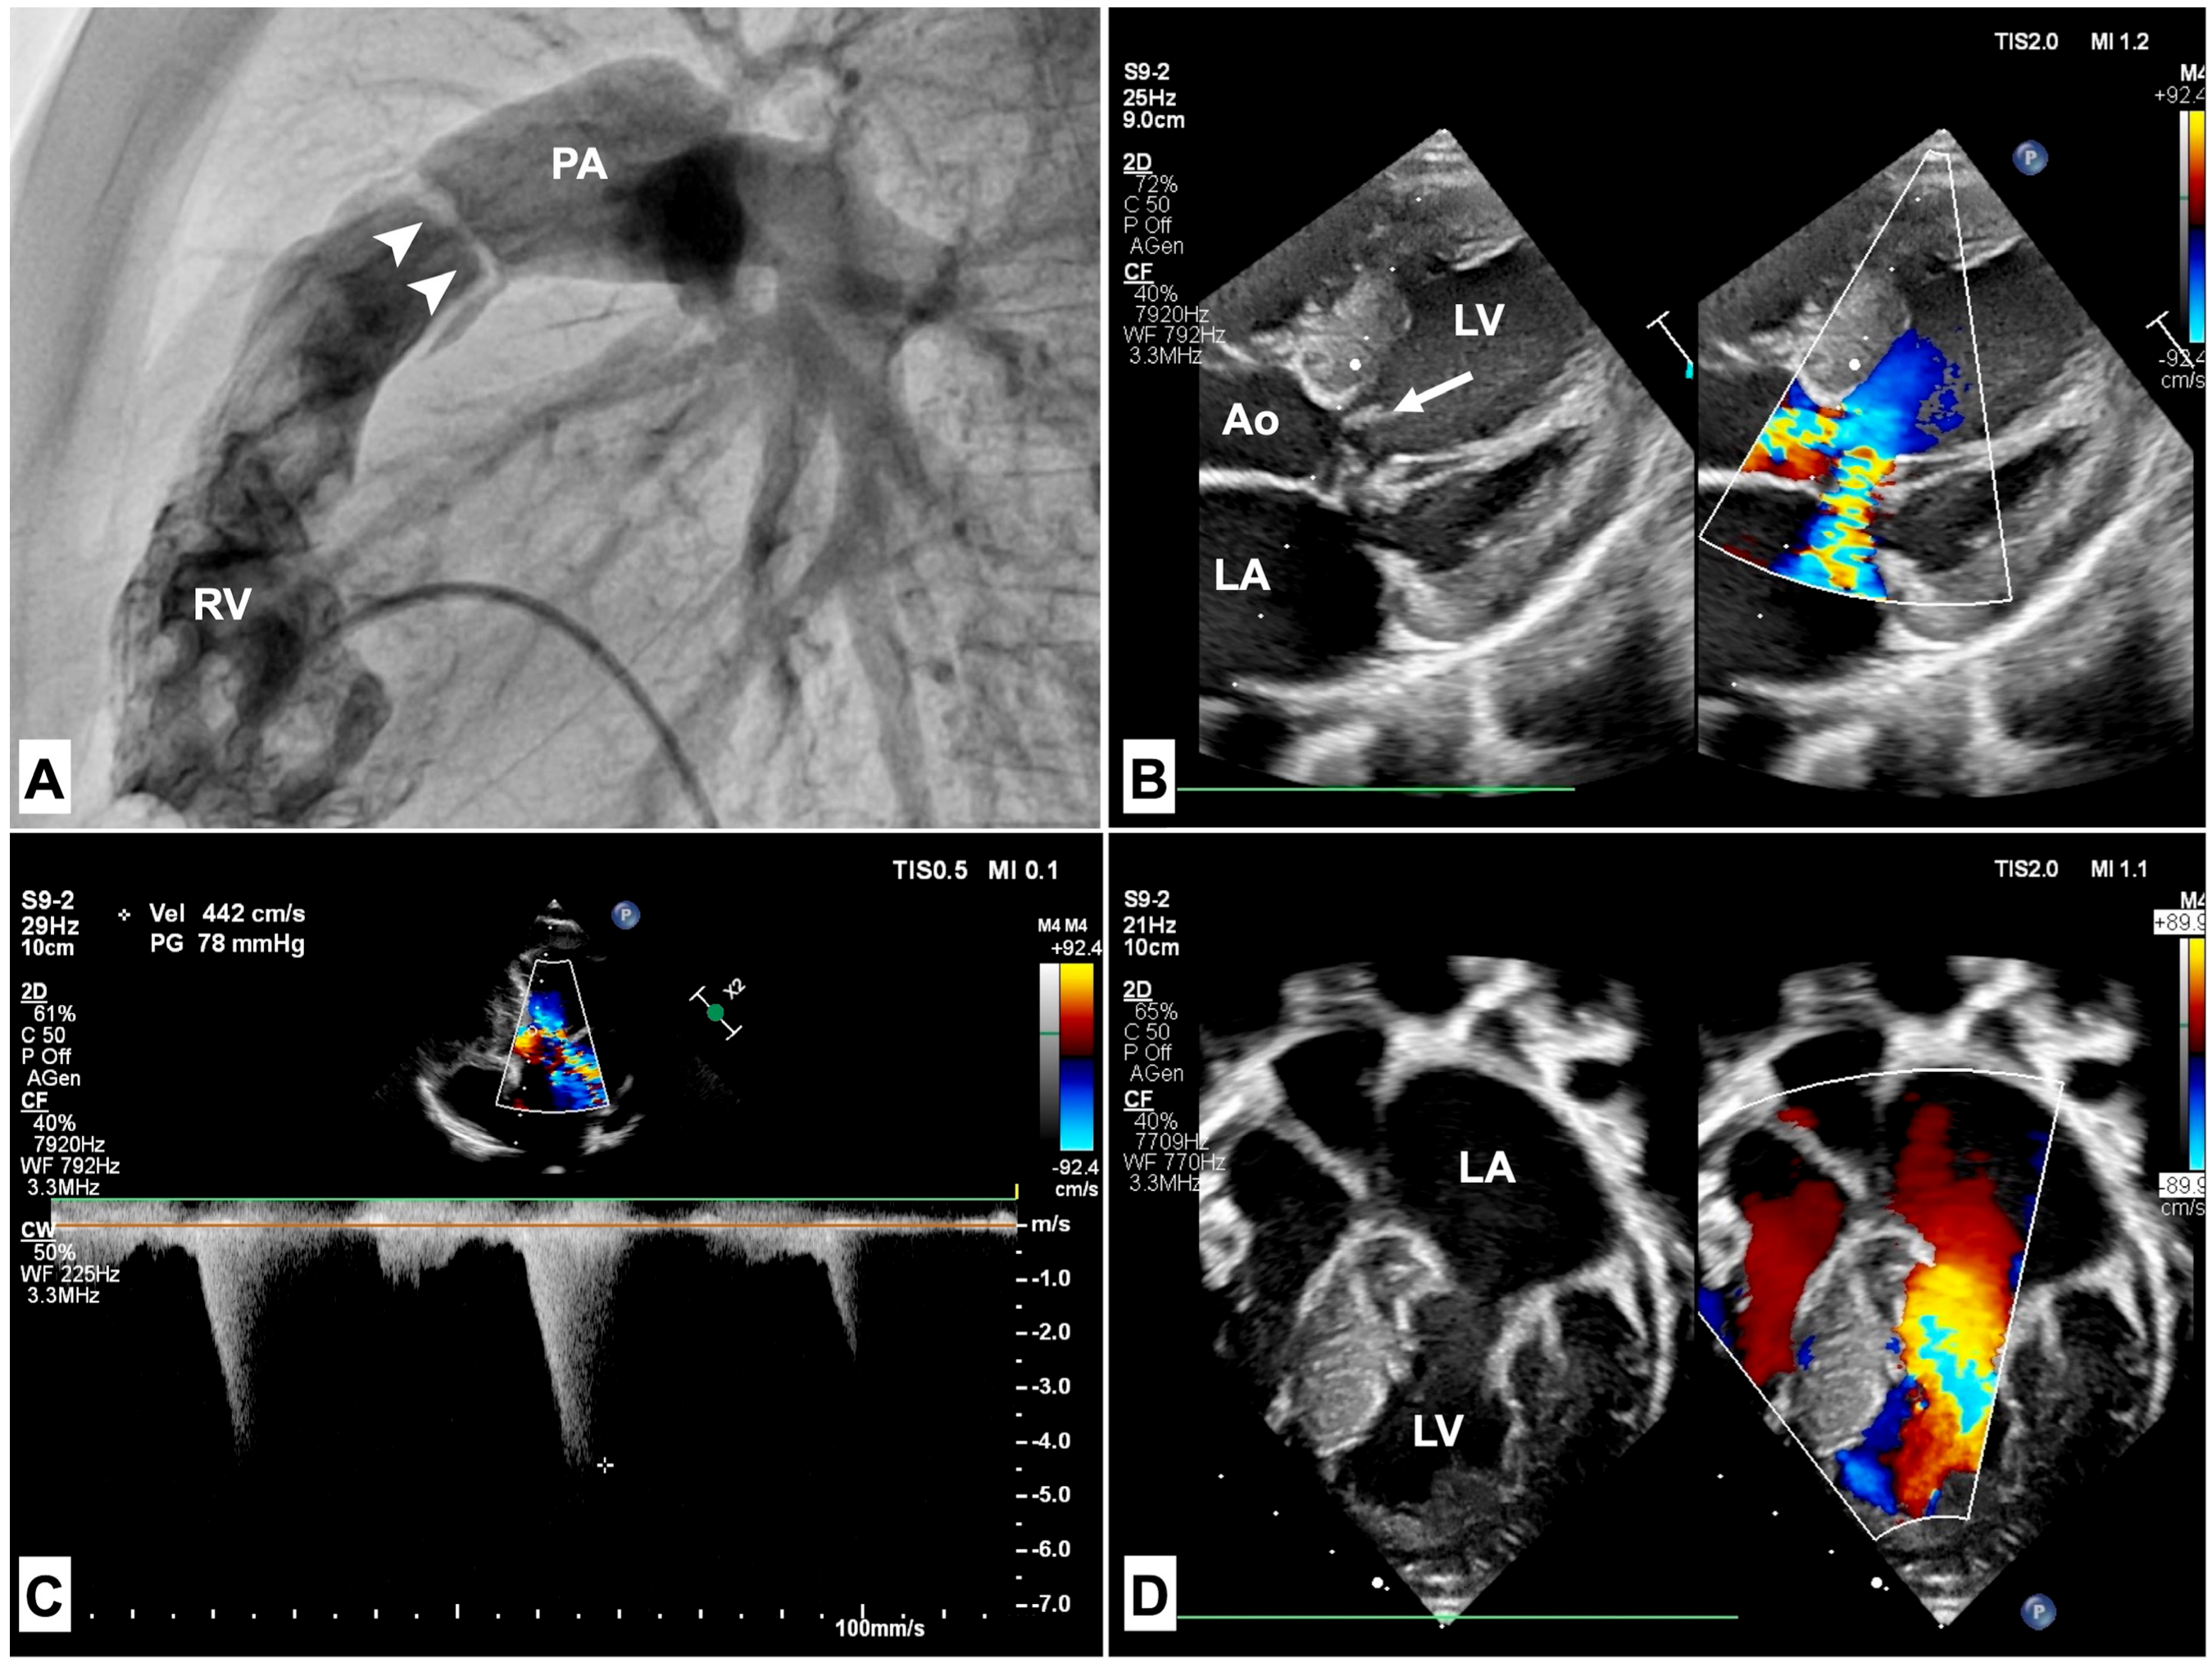

3.1. Pulmonary Stenosis

3.2. Hypertrophic Cardiomyopathy